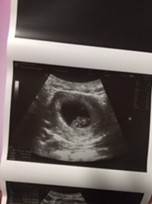

แม่ๆซาวด์เห็นตัวเด็กตอนกี่วีคบ้างคะ เราไปรอบแรกตอน6วีค ไม่เห็นอะไรเลย รอบล่าสุด9วีค ซาวด์เห็นแค่ถุงตามรูปเลยค่ะ เครียดมากเลยค่ะกลัวเป็นท้องลม #ซาวด์แค่หน้าท้องอย่างเดียวนะคะ

ซาวด์เห็นตัวเด็กตอนกี่สัปดาห์